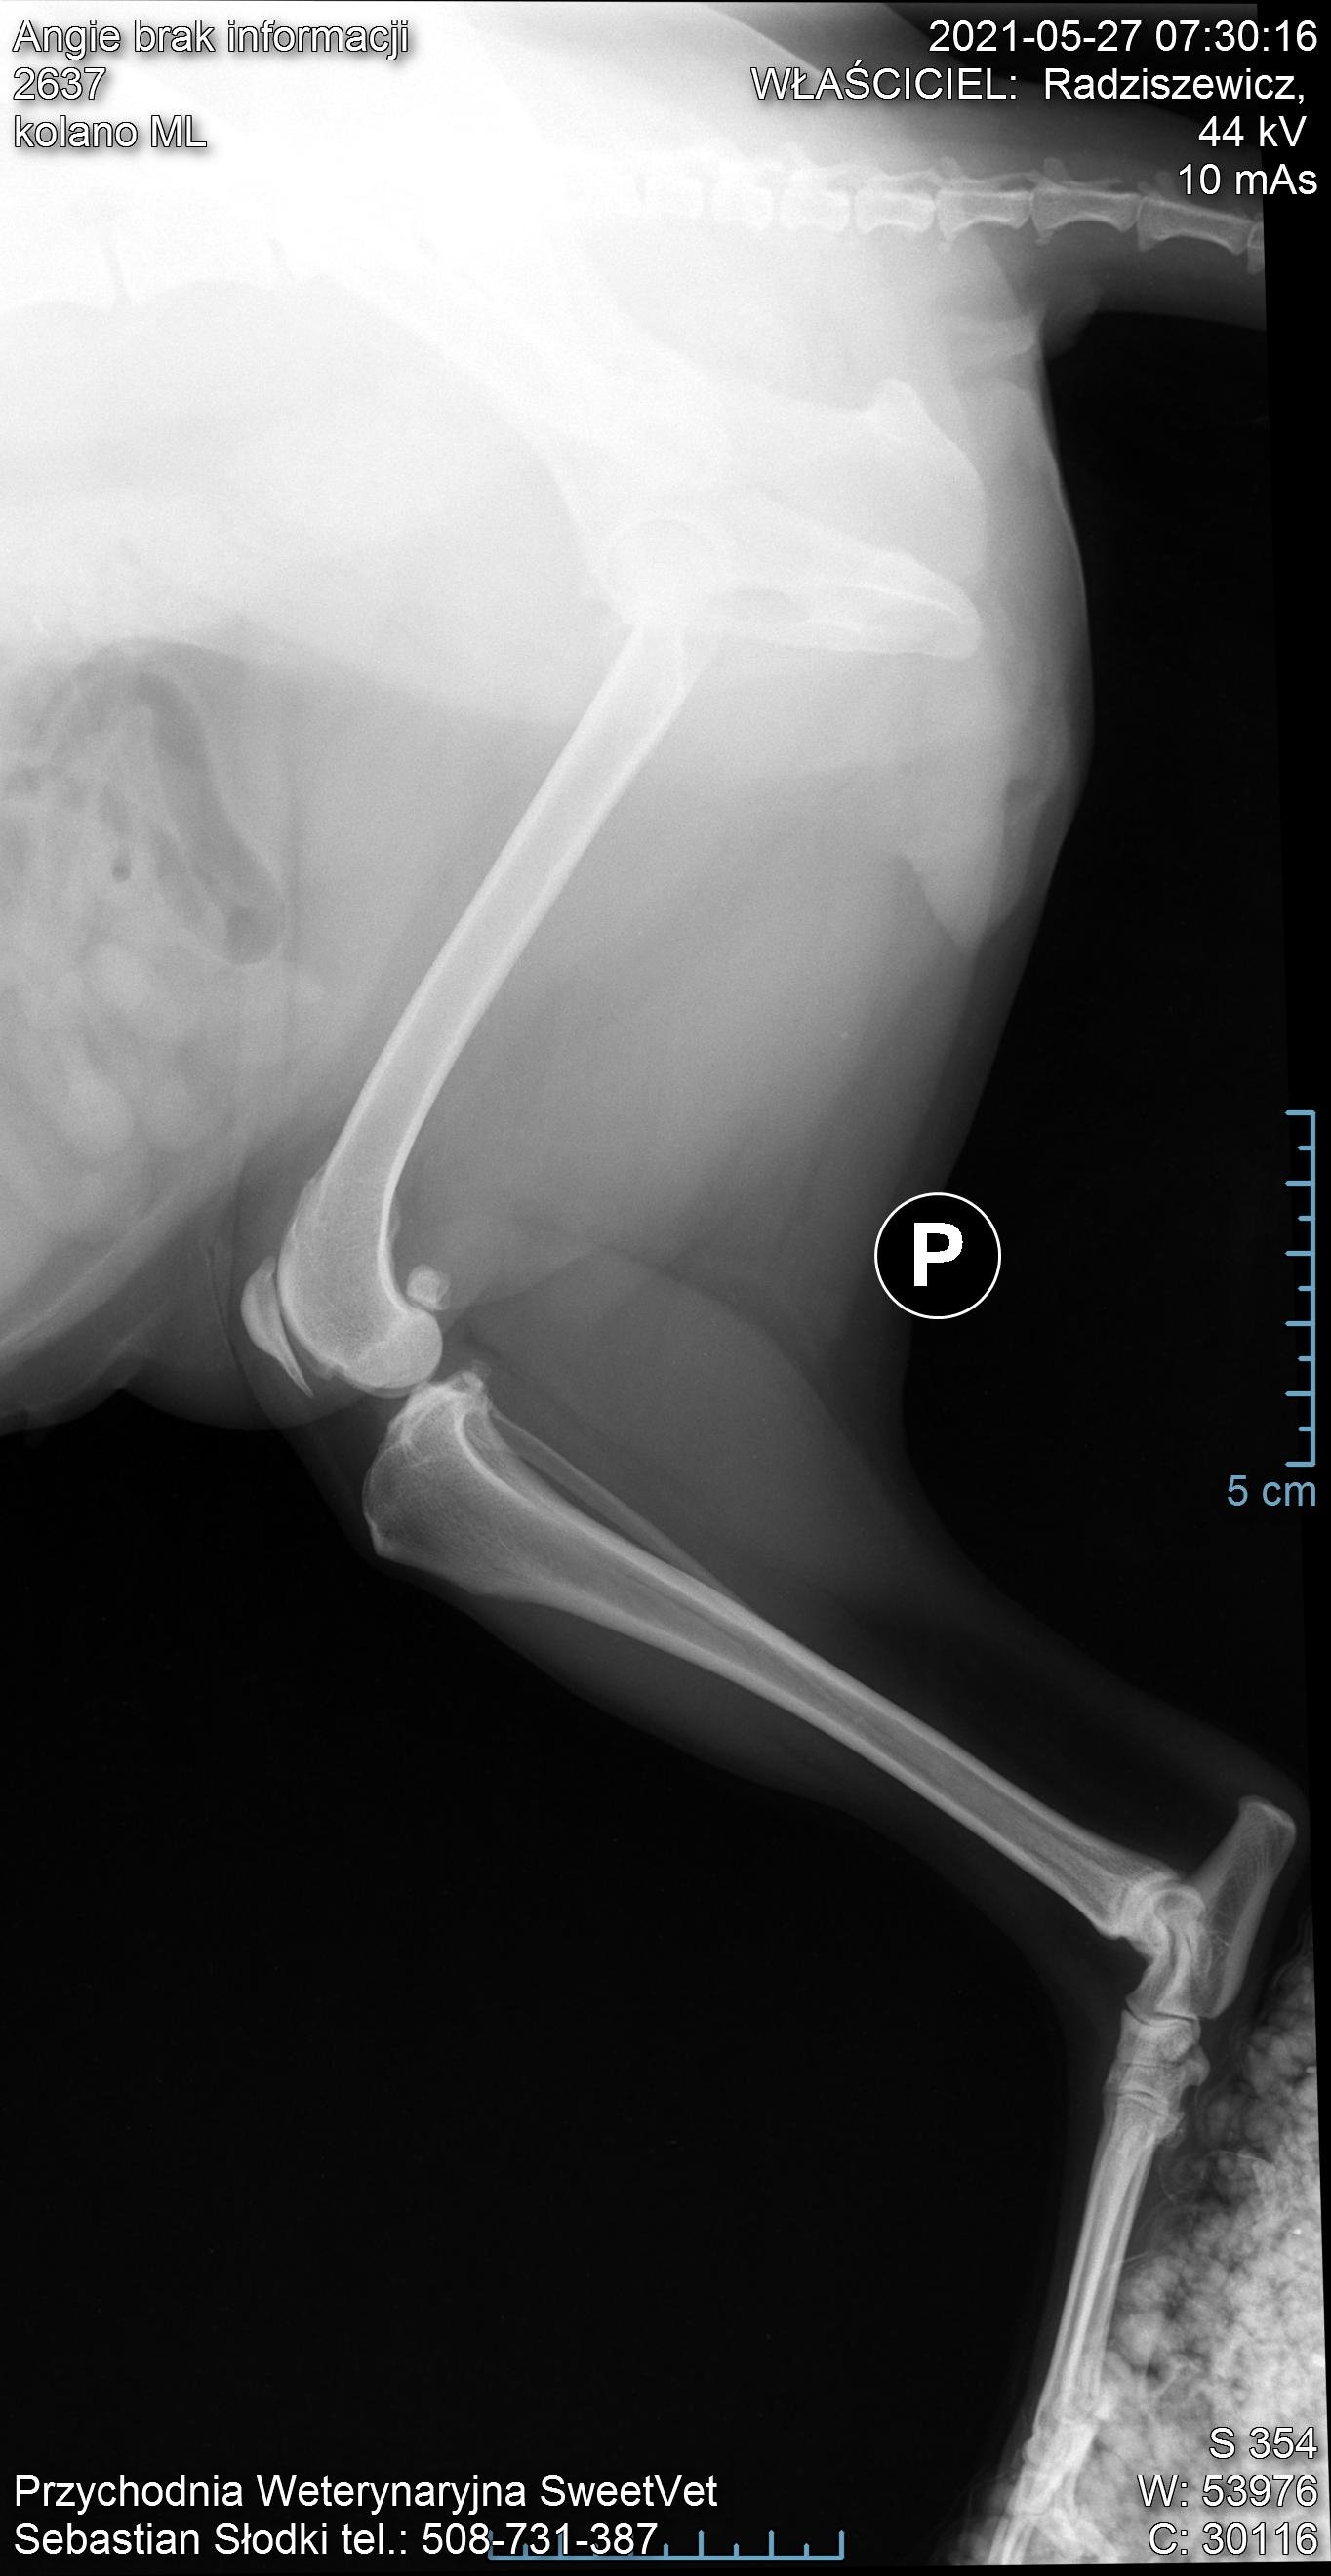

Na nasze szczęście wraz z początkiem maja dostaliśmy możliwość odbywania raz w tygodniu zajęć praktycznych na uczelni w Bydgoszczy. Jako, że mieliśmy opcję przyprowadzić na zajęcia własne zwierzęta i na nich ćwiczyć, zabrałam ze sobą moją Angie. Już na pierwszych zajęciach sunia pokazała dużą bolesność mięśni grzbietu. Tydzień później przy próbach masażu kończyn miednicznych psinka zareagowała agresywnie, od razu dała znać, że nie chce być tam dotykana. Na naszej uczelni przyjmuje fizjoterapeuta zwierząt, więc postanowiłam zaprowadzić tam swojego psa. Okazało się, że mięśnie tylnich łap i kręgosłupa są tak pospinane, że wywołują bardzo dużą bolesność. Przez odciążanie prawej (gorszej) łapki, mięśnie lewej są ciągle spięte, obolałe, przeciążone. Zaczęłyśmy działać przeciwbólowo i rozluźniająco poprzez laseroterapię, ultradźwięki i magnetoterapię. Pani zoofizjoterapeutka poleciła mi jeszcze zrobić dokładne zdjęcia RTG w jednej z bydgoskich klinik (ponieważ bez nich ciężko było wykluczyć bądź potwierdzić wskazania do zabiegu).

Nie zamierzałam się poddać i jeszcze w tym samym tygodniu pojechałam do kliniki Sweetvet na zdjęcia i konsultacje. Okazało się, że mimo tak dużej przestrzeni czasowej od wstępnej diagnozy stawy kolanowe Angie nie są w tragicznym stanie: lewa rzepka-zwichnięcie 2-ego stopnia, prawa- 3-ego. Zdjęcia RTG wykazały zwyrodnienia rzepki i głowy kości udowej w obu kończynach. Bez zabiegu sulkoplastyki i transpozycji guzowatości kości piszczelowej pogłębiające się z czasem zwyrodnienia doprowadzą do zerwania więzadeł. Doktor potwierdził, że Angie jako zdrowy pies, z dobrymi wynikami jak najbardziej nadaje się do operowania, tym bardziej, że teraz jesteśmy w stanie kolosalnie zmienić jej komfort życia.